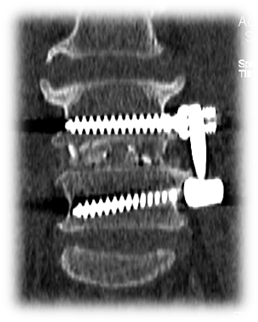

术后 图片2